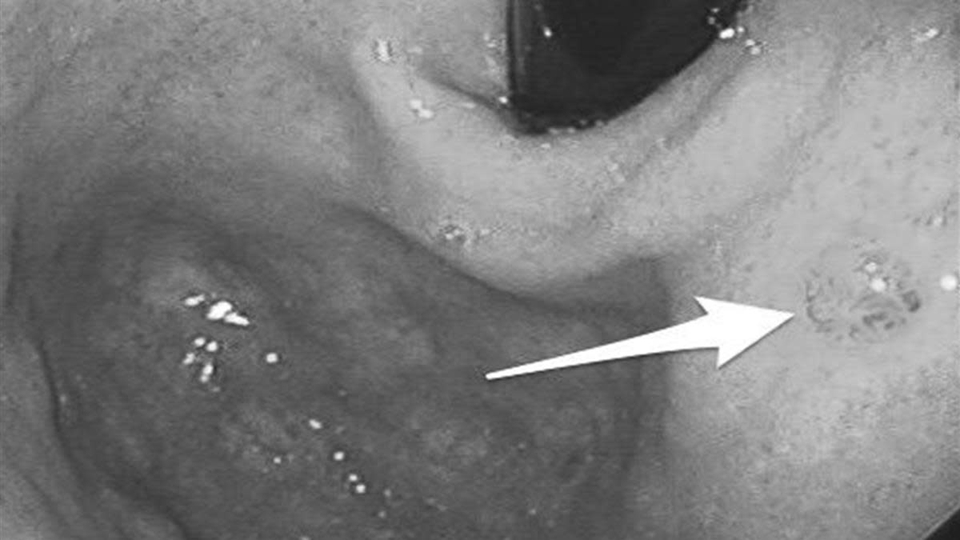

Thực tế, dạ dày không “bỗng nhiên hỏng”. Trước khi chuyển biến xấu, cơ quan này thường phát tín hiệu cảnh báo trong thời gian dài, nhưng vì triệu chứng mơ hồ, nhiều người dễ bỏ qua. Đáng lo hơn, không ít trường hợp chỉ phát hiện khi nội soi, lúc đó nguy cơ đã bước sang giai đoạn trung hoặc muộn.

Theo Cơ quan Nghiên cứu UT Quốc tế (IARC), bệnh thường tiến triển qua một quá trình dài: viêm mạn tính, tổn thương niêm mạc, tăng sinh bất thường rồi mới chuyển thành UT.

Cơ chế này chịu tác động của nhiều yếu tố. Nhiễm vi khuẩn Helicobacter pylori (HP), ăn mặn kéo dài hoặc thói quen sinh hoạt thất thường đều có thể làm suy yếu lớp bảo vệ niêm mạc dạ dày. Khi quá trình tổn thương và sửa chữa lặp lại nhiều lần nhưng không hoàn chỉnh, niêm mạc có thể xuất hiện “chuyển sản ruột” – một dạng tổn thương tiền UT.

Các tổng quan trên tạp chí The Lancet Oncology cho thấy nếu can thiệp từ giai đoạn tiền UT, tiên lượng có thể cải thiện hơn 50%. Tuy nhiên, điểm khó là giai đoạn này hầu như không gây đau dữ dội, mà chỉ là những thay đổi nhẹ, dễ bị xem nhẹ.